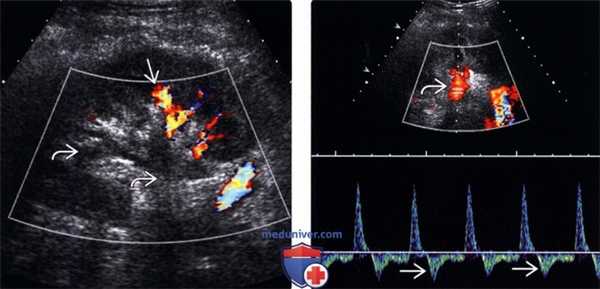

(Левый) На продольном УЗ срезе с цветовой допплерографией визуализируется тромбоз почечной вены трансплантата. Визуализируется тромб в главной почечной вене с распространением на сегментарные вены. Сохранен артериальный кровоток в нижнем полюсе почки.

(Правый) Продольный УЗ срез с цветовой допплерографией у того же пациента. Основная почечная артерия проходима, однако на спектрограмме визуализируется обратный диастолический ток.